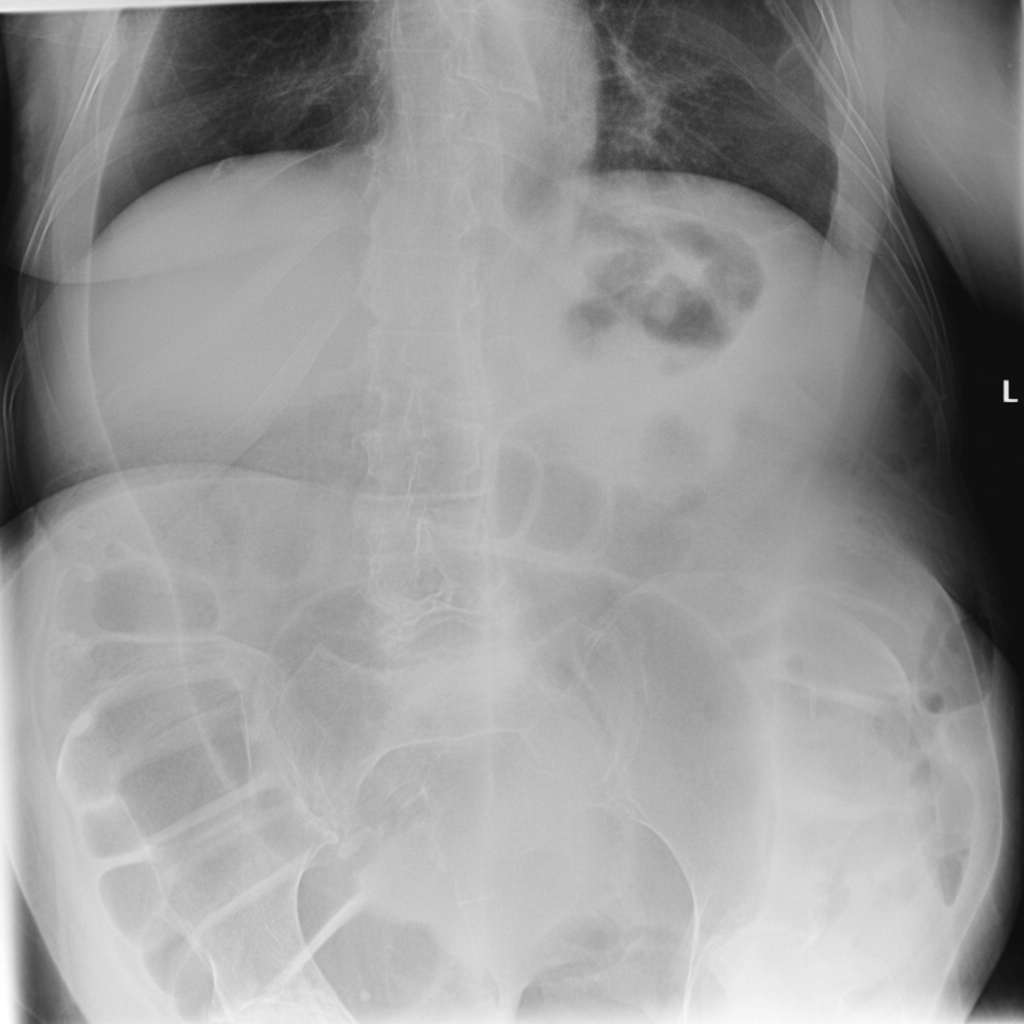

Explanation: ***Sigmoid volvulus*** - The **coffee bean sign** or **omega loop** on plain abdominal X-ray is pathognomonic for sigmoid volvulus, showing the twisted sigmoid colon. - Typically occurs in elderly patients with chronic constipation and presents with **acute large bowel obstruction** and abdominal distension. *Adhesive obstruction* - Usually causes **small bowel obstruction** with dilated small bowel loops and air-fluid levels on X-ray. - Associated with **previous abdominal surgery** and presents with colicky abdominal pain and vomiting. *Meckel's diverticulum* - A **true diverticulum** of the small bowel that rarely causes obstruction in adults. - More commonly presents with **GI bleeding** or **intussusception** in children, not the classic radiological sign described. *Gastric volvulus* - Involves twisting of the **stomach** rather than the sigmoid colon. - Presents with **Borchardt's triad** (severe epigastric pain, retching without vomiting, inability to pass NGT) and different radiological appearance.